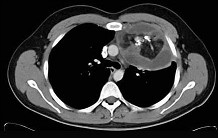

- 单项选择题20岁,男, 左胸痛伴压迫感,咳嗽1个月, 请结合CT,检查选出最可能的诊断 ( )

A、胸腺瘤

B、纵隔血肿

C、畸胎瘤

D、脂肪瘤

E、淋巴瘤